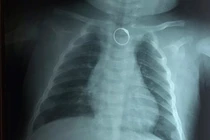

Dị vật kim loại kích thước lớn nếu không được xử lý kịp thời có thể gây tắc nghẽn thực quản, tổn thương niêm mạc, đe dọa tính mạng nếu tràn sang đường thở.

Các bác sĩ Bệnh viện Sản Nhi tỉnh Vĩnh Phúc đã gắp thành công một đồng xu kim loại có hình tròn đường kính 3cm từ trong thực quản cháu bé 4 tuổi ra ngoài.

BVĐK Xuyên Á vừa tiếp nhận bé gái 2 tuổi nuốt phải chiếc nhẫn vàng đeo trên ngón tay, khiến dị vật trôi vào thực quản, gây khó thở, sặc sụa. Một bé trai khác 4 tuổi cũng phải cấp cứu vì hóc đồng xu…

Trong lúc cầm chơi đồng xu, bé L. 5 tuổi (bé gái), ngụ tại huyện Hóc Môn, TPHCM đã bỏ đồng xu vào miệng và bị mắc tại thực quản, được các bác sĩ của Trung tâm Nội soi BV Đa Khoa Xuyên Á gắp ra thành công – TS.BS Nguyễn Văn Châu, Tổng Giám đốc BV Đa khoa Xuyên Á vừa cho biết.